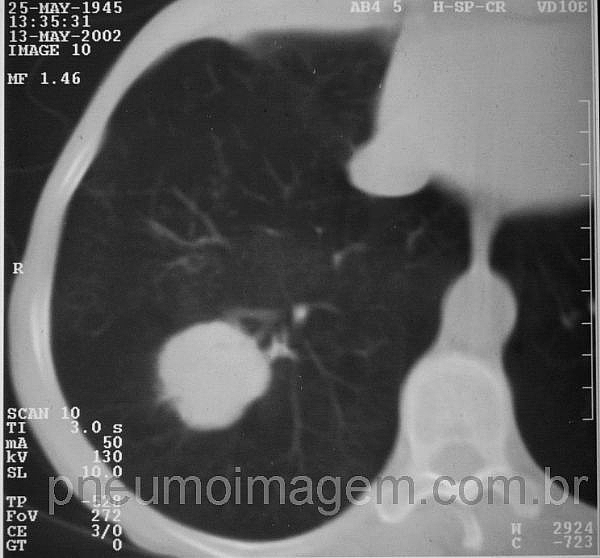

Para ver imagens de câncer de pulmão no PneumoImagem, clique aqui.